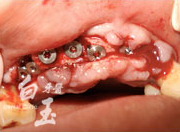

植入植體